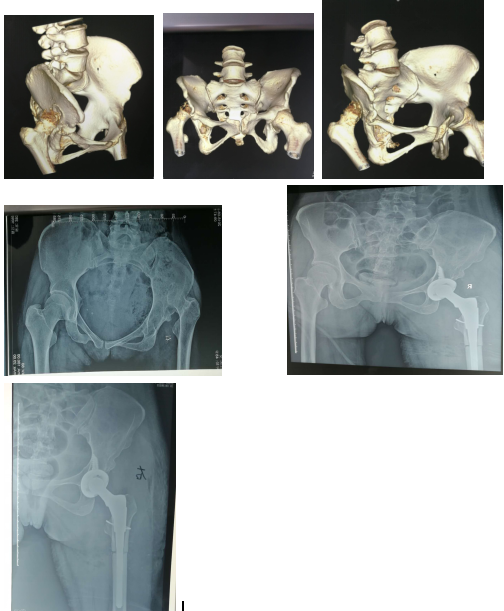

1. 先天性髋臼发育不良(CDH)、先天性髋关节脱位(LCP)、股骨头骨骺滑脱(SCFE)等。如患者全身情况好,肌肉肌腱系统可发挥正常功能,病人合作,术后配合良好的康复训练,符合条件者可考虑采用人工关节置换术。过去认为60-75岁之间为人工关节置换的最佳年龄,但在近年来,这个年龄范围已得到放宽,许多高龄患者同时也有很多更年轻的病人都被认为可以采用人工关节置换手术治疗。我科近年来治疗先天性髋关节脱位,行人工关节置换术取得良好效果。附典型案例如下: